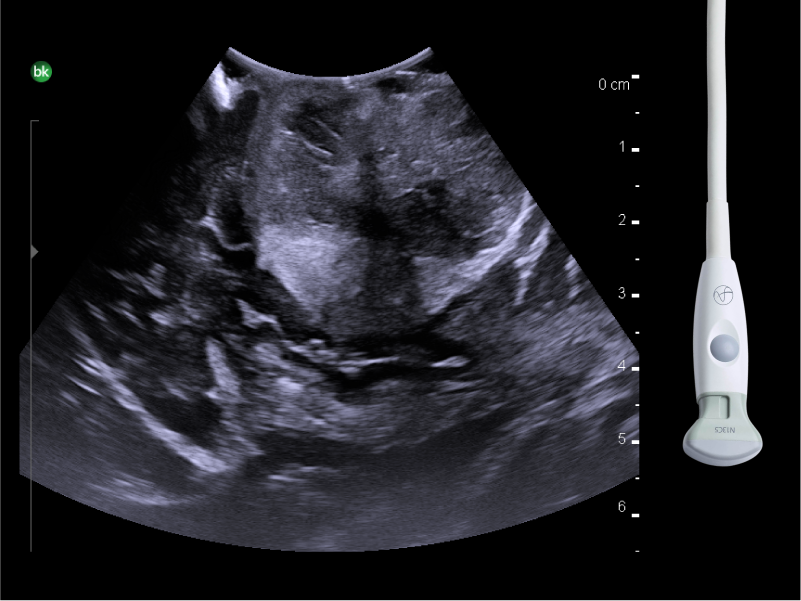

REAL-TIME VISUALIZATION HAS NEVER LOOKED THIS GOOD

- Enhanced Visualization: Improved algorithms for greater details around lesion borders, and automated high-resolution image settings.

- Monitor Progress: Compare live images with previous scans simultaneously using Dual Live Compare, Picture in Picture, or Stored Image Compare.